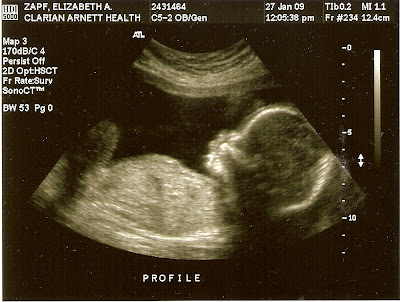

So, here is “New Baby” at 20 weeks:

I didn’t add any captions because the ultrasound tech did such a lovely job of it, I didn’t want to attempt to out-do her.